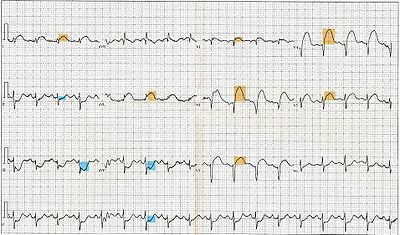

Electrocardiogram

The primary purpose of the electrocardiogram is to detect ischemia or acute coronary injury in broad, symptomatic emergency department populations. However, the standard 12 lead ECG has several limitations. An ECG represents a brief sample in time. Because unstable ischemic syndromes have rapidly changing supply versus demand characteristics, a single ECG may not accurately represent the entire picture. It is therefore desirable to obtain serial 12 lead ECGs, particularly if the first ECG is obtained during a pain-free episode. Alternatively, many emergency departments and chest pain centers use computers capable of continuous ST segment monitoring. The standard 12 lead ECG also does not directly examine the right ventricle, and is relatively poor at examining the posterior basal and lateral walls of the left ventricle. In particular, acute myocardial infarction in the distribution of the circumflex artery is likely to produce a nondiagnostic ECG. The use of additional ECG leads like right-sided leads V3R and V4R and posterior leads V7, V8, and V9 may improve sensitivity for right ventricular and posterior myocardial infarction. In spite of these limitations, the 12 lead ECG stands at the centre of risk stratification for the patient with suspected acute myocardial infarction. Mistakes in interpretation are relatively common, and the failure to identify high risk features has a negative effect on the quality of patient care.

The 12 lead ECG is used to classify patients into one of three groups:

- those with ST segment elevation or new bundle branch block (suspicious for acute injury and a possible candidate for acute reperfusion therapy with thrombolytics or primary PCI),

- those with ST segment depression or T wave inversion (suspicious for ischemia), and

- those with a so-called non-diagnostic or normal ECG.

A normal ECG does not rule out acute myocardial infarction. Sometimes the earliest presentation of acute myocardial infarction is the hyperacute T wave, which is treated the same as ST segment elevation. In practice this is rarely seen, because it only exists for 2-30 minutes after the onset of infarction. Hyperacute T waves need to be distinguished from the peaked T waves associated with hyperkalemia. The current guidelines for the ECG diagnosis of acute myocardial infarction require at least 1 mm (0.1 mV) of ST segment elevation in the limb leads, and at least 2 mm elevation in the precordial leads. These elevations must be present in anatomically contiguous leads. (I, aVL, V5, V6 correspond to the lateral wall; V1-V4 correspond to the anterior wall; II, III, aVF correspond to the inferior wall.) This criterion is problematic, however, as acute myocardial infarction is not the most common cause of ST segment elevation in chest pain patients. Over 90% of healthy men have at least 1 mm (0.1 mV) of ST segment elevation in at least one precordial lead. The clinician must therefore be well versed in recognizing the so-called ECG mimics of acute myocardial infarction, which include left ventricular hypertrophy, left bundle branch block, paced rhythm, early repolarization, pericarditis, hyperkalemia, and ventricular aneurysm.

Left bundle branch block and pacing interferes with the electrocardiographic diagnosis of acute myocadial infarction by making the ST segment uninterpretable. The GUSTO investigators Sgarbossa et al. developed a set of criteria for identifying acute myocardial infarction in the presence of left bundle branch block and paced rhythm. They include concordant ST segment elevation > 1 mm (0.1 mV), discordant ST segment elevation > 5 mm (0.5 mV), and concordant ST segment depression in the left precordial leads. The presence of reciprocal changes on the 12 lead ECG may help distinguish true acute myocardial infarction from the mimics of acute myocardial infarction. The contour of the ST segment may also be helpful, with a straight or upwardly convex (non-concave) ST segment favoring the diagnosis of acute myocardial infarction.

The constellation of leads with ST segment elevation enables the clinician to identify what area of the heart is injured, which in turn helps predict the so-called culprit artery.

As the myocardial infarction evolves, there may be loss of R wave height and development of pathological Q waves (defined as Q waves deeper than 1 mm and wider than 1 mm.) T wave inversion may persist for months or even permanently following acute myocardial infarction. Typically, however, the T wave recovers, leaving a pathological Q wave as the only remaining evidence that an acute myocardial infarction has occurred.